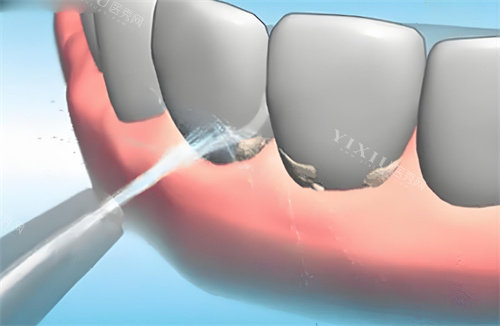

洗牙:

超声波洁牙:180元起/次

喷砂洁牙:260元起/次